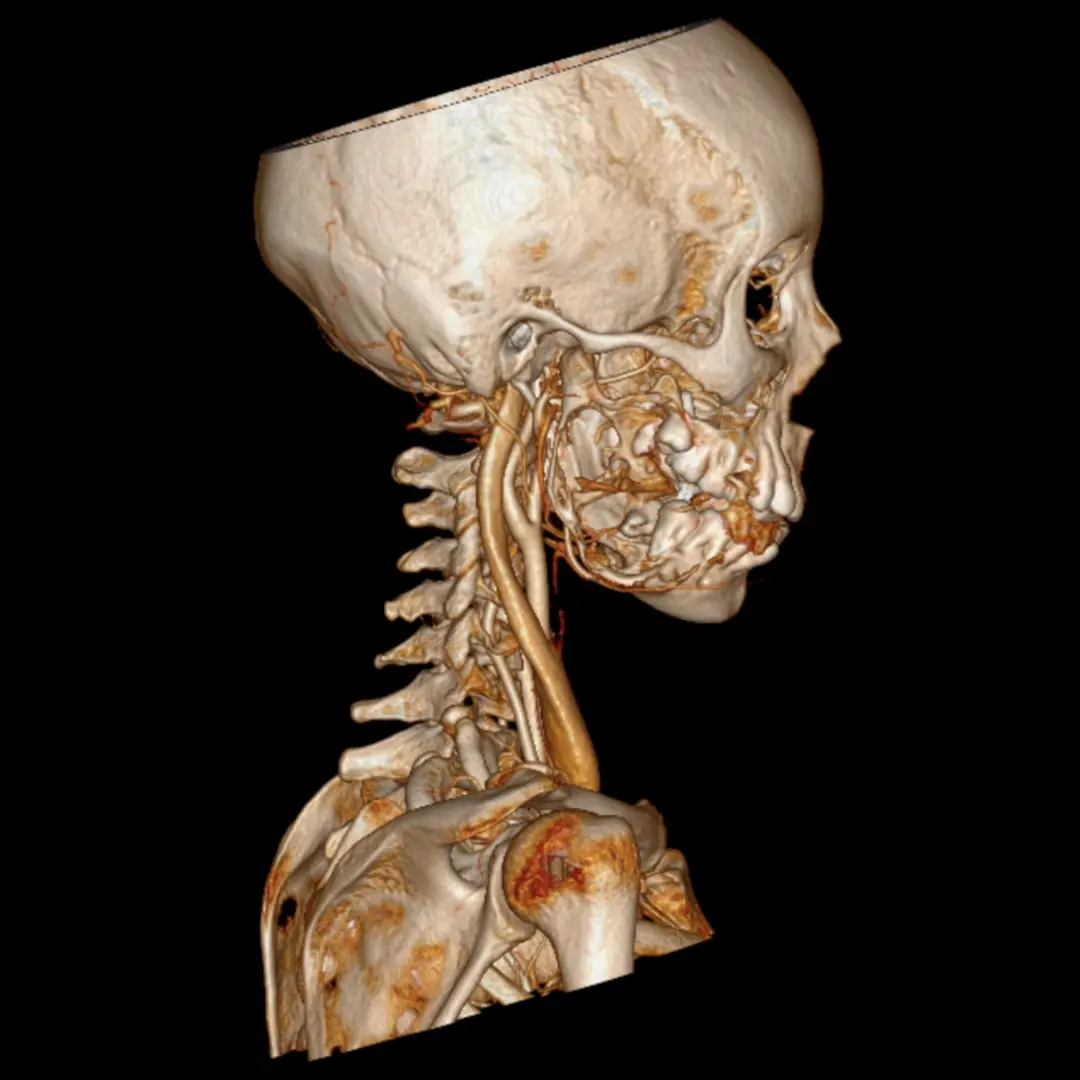

Cirugía ortognática (asimetrías faciales)

Corrección quirúrgica de deformidades óseas en mandíbula y maxilares para mejorar estética, mordida y respiración.

La cirugía ortognática, del griego orthos, «recto» y gnathos, «mandíbula», es una intervención quirúrgica que se encarga de corregir las deformidades dento-craneo-maxilofaciales mediante movimientos óseos maxilares y mandibulares, para lograr el equilibrio perfecto entre todas las características faciales del paciente.

Este tipo de alteraciones faciales aparecen en la fase de crecimiento de los pacientes, se estabilizan al final de la misma, y pueden causar problemas como apnea del sueño, trastornos de la ATM, problemas de maloclusión o falta de armonía esquelética, entre otros.